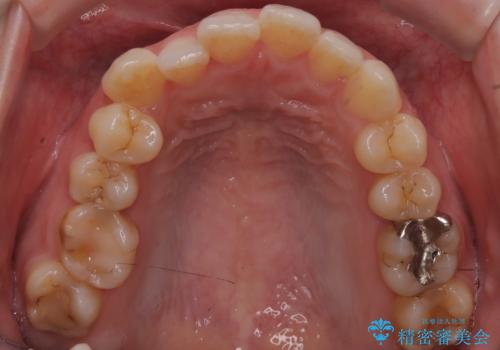

- 治療計画

今回のワイヤー矯正治療では、抜歯せずに歯を並べるスペースを作るため、特殊な小さなインプラントであるアンカースクリュー(TAD)を一時的に使用しました。このアンカースクリューを固定源として、奥歯(臼歯部)全体を後方へ遠心移動させました。従来の矯正では難しかったこの奥歯の移動を確実に行うことで、前歯の八重歯を適切な位置に並べるスペースを確保。治療の結果、抜歯することなく右上の八重歯と叢生が解消され、機能的にも審美的にも整った美しい歯並びを獲得していただけました。